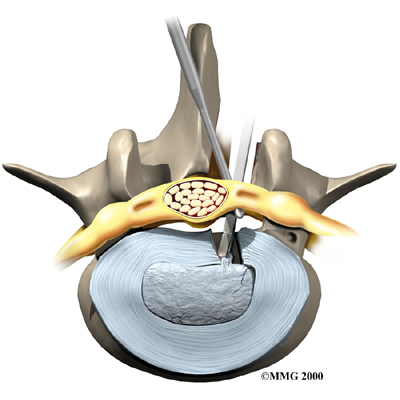

Microdiscectomy

Microdiscectomy is becoming the standard surgery for lumbar disc herniation. The procedure is used when a herniated disc is putting pressure on a nerve root. It involves carefully taking out part of the problem disc (discectomy). By performing the operation with a surgical microscope, the surgeon only needs to make a very small incision in the low back. Categorized as minimally invasive surgery, this surgery is thought to be less taxing on patients. Advocates also believe that this type of surgery is easier to perform, that it prevents scarring around the nerves and joints, and that it helps patients recover more quickly.

Related Document: FYZICAL Greenville's Guide to Lumbar Discectomy